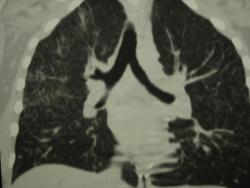

девушка 1985 г.р. дообследована после профилактической флюорографии, на КТ написали гистиоцитоз. Диагноз пока не подтвержден. Жалоб не предъявляет, курит в течение 8-9 лет. консультирована у фтизиатров, свою патологию они исключили.

На мой взгляд, выражены два компонента:

- преимущественно мономорфная диссеминации;

- интерстициальный компонент.

Но, КТ, по всей видимости, свидетельствует, именно, о диффузности процесса, с некоторым превалированием в отдельных отделах.